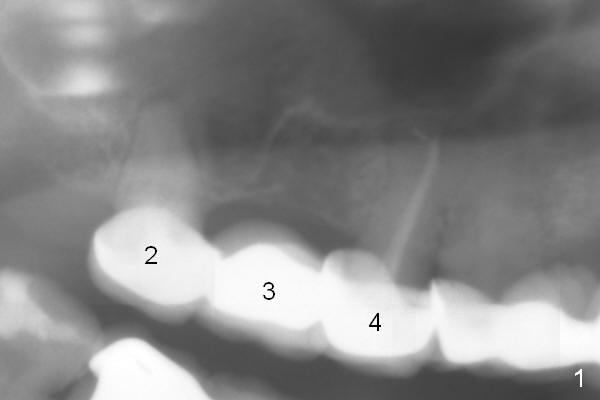

A 47-year-old woman has multiple restoration.  When #2-4 FPD ( is recemented, the 2 abutments are found nonsalvageable.  To avoid sinus complications, implants at these 3 sites will be long enough, but do not penetrate the sinus floor unless primary stability cannot be obtained (Fig.2).  Underprep is a must, particularly for immediate implants.  Since the bone density at the site of #3 is low, bone expansion is to be conducted.